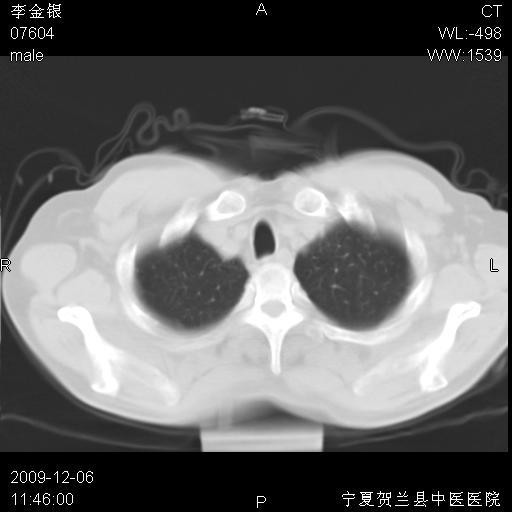

该病人 ,男,62岁,主因咳痰带血两天

支气管壁明显增厚 管腔狭窄,腔静脉后多个淋巴肿大,结合年龄病史考虑右肺上叶中央型肺癌并阻塞性肺炎

右肺上叶后段支气管阻塞,右上肺门占位,相应肺段阻塞性肺炎,右肺门有淋巴结肿大。诊断右肺上叶中心型肺癌,阻塞性肺肺炎、右肺门淋巴结转移。

右上叶支气管狭窄,管壁增厚,远端斑片状软组织影,病灶邻近叶间裂,叶间裂无移位。

诊断右肺中央型肺癌。

那个片影应该大部分都是病灶,病灶沿肺段支气管分支生长,后段完全显示不清、闭塞。若为不张应该伴有叶裂的移位,若为炎症应有空气支气管征。

右肺中心型肺癌伴阻塞性肺炎及右肺门与纵膈淋巴结转移很典型,可纤维支气管镜进一步检查

考虑右侧中央型肺癌伴右肺上叶后段阻塞性炎症、肺不张、右肺门和纵隔淋巴结肿大。